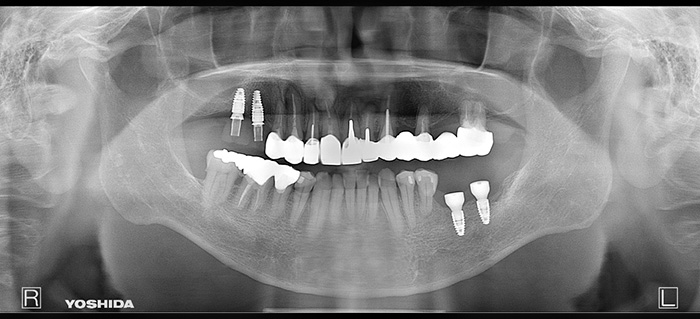

右上臼歯部2本・左下臼歯部2本にインプラント治療を行った症例です。

欠損部に対しインプラントを埋入し、咀嚼機能の回復と咬合バランスの改善を行いました。周囲歯への負担を抑えながら、固定性のある補綴装置により安定した噛み心地を目指した治療です。

【右上臼歯部インプラント治療】インプラント埋入手術および上部構造装着(2本)

【左下臼歯部インプラント治療】インプラント埋入手術および上部構造装着(2本)

欠損部のインプラント治療と金属修復をセラミックへ置き換えた包括的治療症例

患者様は、左下の欠損部の改善と、口腔内にある金属修復物を白い材質に変更したいとのご希望で来院されました。

機能的回復と審美性の改善の両面から、包括的な治療が必要な状態でした。

以下の治療を行いました。

本症例では、機能性と審美性のバランスを考慮した材料選択を行っています。

奥歯については、咬合力が強くかかるため、色調よりも強度を優先し、ジルコニアスタンダードを使用しました。

一方で前歯部は、周囲歯との色調調和が重要であるため、より審美性に優れたジルコニアプレミアムを選択しています。

また、欠損部にはインプラント治療を行うことで、周囲の歯に負担をかけずに咬合機能の回復を図っています。

口腔内全体を一つの単位として治療計画を立てることで、機能面・審美面ともにバランスの取れた結果を目指しました。

欠損部の咬合が回復し、奥歯でしっかり噛める状態となりました。

また、金属修復物がセラミックに置き換わることで、口腔内全体の審美性が向上しています。